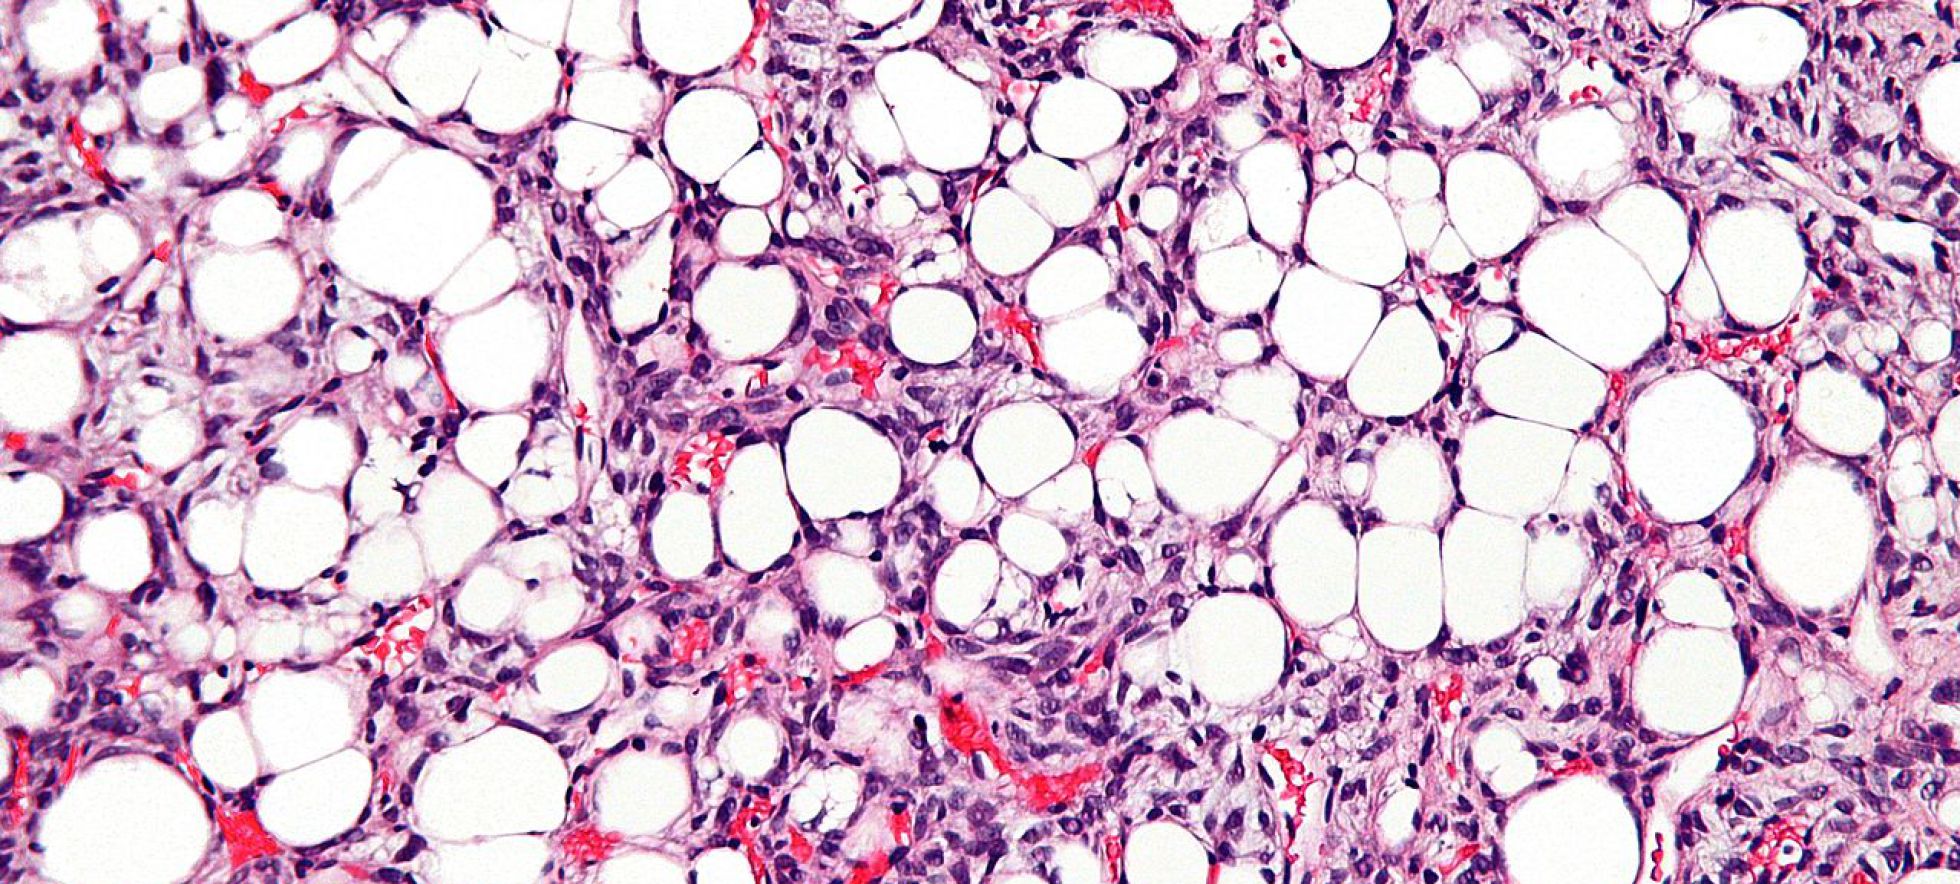

"Solo son candidatos quienes ya hayan recibido algún tratamiento y hayan fracasado", añade Ramón Cubedo, el médico del hospital que quiere entrar en ese ensayo mundial para el que buscan, en todo el mundo, a 30 afectados. El liposarcoma es un cáncer de la grasa que está entre las fibras musculares –"como las vetas del jamón", explica el médico– o en otros acúmulos. A Gómez, por ejemplo, le apareció en la zona retroperitoneal, "donde los riñones". "Me sentía cansado, y no encontraban por qué. Al final me quitaron una masa de grasa de más de 10 kilos", relata. "No se sabe cuándo empezó. A veces va muy deprisa, y, a veces, muy despacio", indica. Esa fue su primera operación. En la segunda, la masa tumoral le desplazó un riñón, y hubo que extirpárselo.

La causa de la enfermedad es genética. Al menos, se han identificado dos mutaciones asociadas. "Son el crimen perfecto", ejemplifica el médico: "Una confiere a las células la capacidad de multiplicarse de manera infinita; la otra, la de la inmortalidad". A paliar su efecto va el medicamento desarrollado por Novartis. Ese que necesita voluntarios para comprobar si funciona.